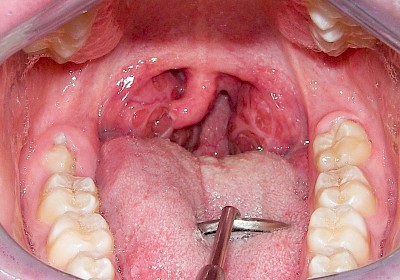

Mandelentzündung

Mandelentzündungen (Tonsillitis) zeigen häufig Rötungen, Schwellungen oder eitriges Sekret im Bereich der jeweiligen Mandel und sollten direkt ärztlich abgeklärt werden. Vielen Menschen wurde vor allem in der Kindheit ein- oder beidseitig die Mandeln entfernt, um die Atmung zu erleichtern. So können im Bereich der Gaumenbögen Vernarbungen oder Seitenunterschiede auffallen. Zudem können nach Mandelentfernungen (Tonsillektomie) die Infektanfälligkeit erhöht sein, da die Mandeln ja Bestandteil der Immunabwehr sind.

Bei Vergrößerung der Gaumenmandeln (Hyperplasie) z.B. infolge chronischer Entzündungenkann die Belüftung der Ohren gestört sein und es kann zu Schnarchen mit Atemaussetzern (Apnoe) sowie zu Schluckstörungen kommen. Bei entsprechenden Auffälligkeiten sollte eine ärztliche Abklärung erfolgen.